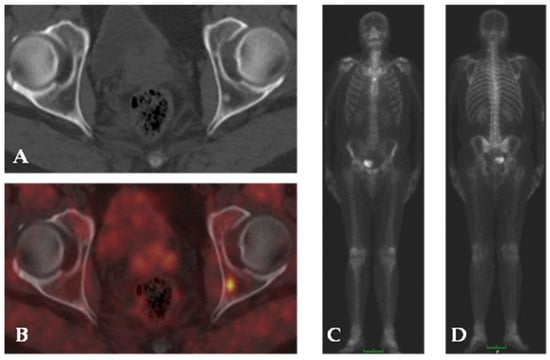

4.2. Choline

- Fuccio, C.; Castellucci, P.; Schiavina, R.; Santi, I.; Allegri, V.; Pettinato, V.; Boschi, S.; Martorana, G.; Al-Nahhas, A.; Rubello, D.; et al. Role of 11C-Choline PET/CT in the Restaging of Prostate Cancer Patients Showing a Single Lesion on Bone Scintigraphy. Ann. Nucl. Med. 2010, 24, 485–492. [Google Scholar] [CrossRef] [PubMed]

- Klain, M.; Gaudieri, V.; Petretta, M.; Zampella, E.; Storto, G.; Nappi, C.; Buonerba, C.; Crocetto, F.; Gallicchio, R.; Volpe, F.; et al. Combined Bone Scintigraphy and Fluorocholine PET/Computed Tomography Predicts Response to Radium-223 Therapy in Patients with Prostate Cancer. Future Sci. OA 2021, 7, FSO719. [Google Scholar] [CrossRef] [PubMed]